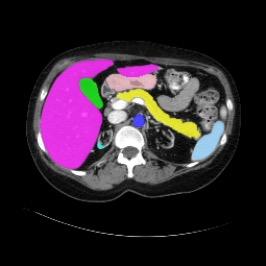

Integrating high-level semantically correlated contents and low-level anatomical features is of central importance in medical image segmentation. Towards this end, recent deep learning-based medical segmentation methods have shown great promise in better modeling such information. However, convolution operators for medical segmentation typically operate on regular grids, which inherently blur the high-frequency regions, i.e., boundary regions. In this work, we propose MORSE, a generic implicit neural rendering framework designed at an anatomical level to assist learning in medical image segmentation. Our method is motivated by the fact that implicit neural representation has been shown to be more effective in fitting complex signals and solving computer graphics problems than discrete grid-based representation. The core of our approach is to formulate medical image segmentation as a rendering problem in an end-to-end manner. Specifically, we continuously align the coarse segmentation prediction with the ambiguous coordinate-based point representations and aggregate these features to adaptively refine the boundary region. To parallelly optimize multi-scale pixel-level features, we leverage the idea from Mixture-of-Expert (MoE) to design and train our MORSE with a stochastic gating mechanism. Our experiments demonstrate that MORSE can work well with different medical segmentation backbones, consistently achieving competitive performance improvements in both 2D and 3D supervised medical segmentation methods. We also theoretically analyze the superiority of MORSE.

翻译:在医学图像分割中,整合高级语义相关的内容和低级解剖特征对于模拟这些信息非常重要。近期基于深度学习的医学分割方法已经显示出很有前景,可以更好地建模这些信息。然而,医学分割的卷积运算符通常在正则化网格上运作,这在本质上模糊了高频区域,即边界区域。我们在这项工作中提出了 MORSE,这是一个设计在解剖学水平上的通用隐式神经渲染框架,用于协助医学图像分割的学习。我们的方法的动机在于隐式神经表示已经被证明比离散化网格表示更有效地拟合复杂信号和解决计算机图形问题。我们方法的核心是将医学图像分割连续地对准粗糙的分割预测和模棱两可的基于坐标的点表示,并聚合这些特征来自适应地精细化边界区域。为了并行地优化多尺度像素级特征,我们借鉴了 Mixture-of-Expert (MoE) 的思想设计和训练我们的MORSE,使用随机门控机制。我们的实验表明MORSE可以很好地与不同的医学分割后骨干结合在一起,始终在2D和3D监督医学分割方法中实现了有竞争力的性能改进。我们还从理论上分析了MORSE的优越性。